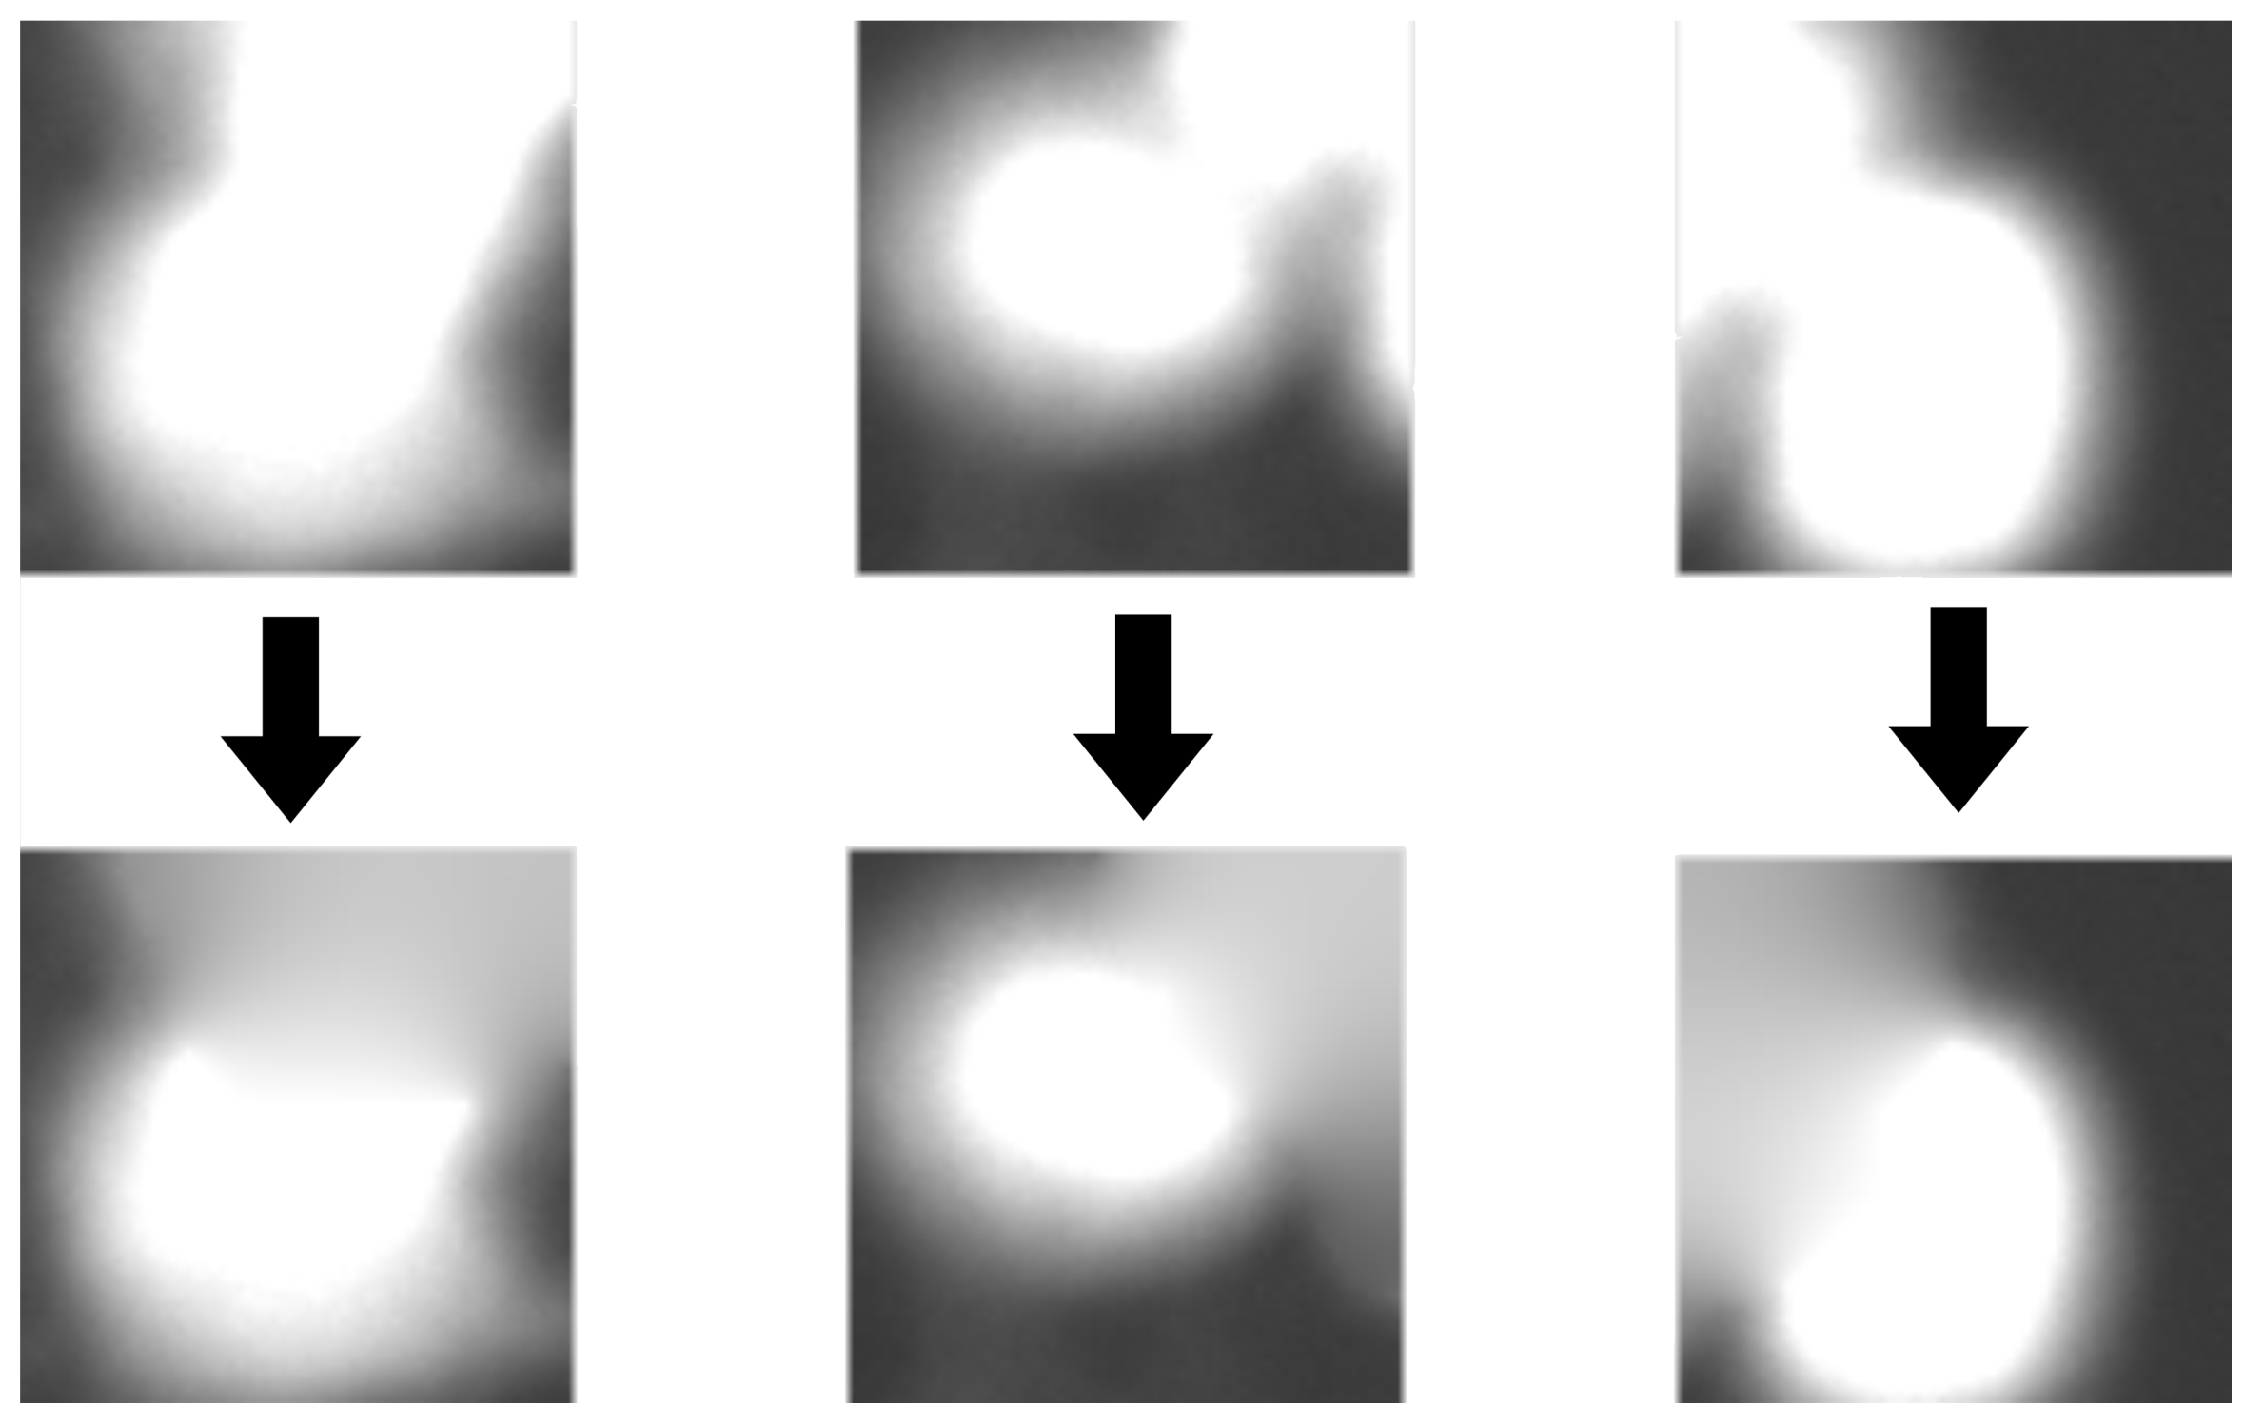

Patches extracted during the previous stage contain not only the desired cells, but also parts of neighboring objects. In order to perform an effective classification process, we have to inpaint those areas. We achieve this by using watershed transform for the second time, this time on GFP images, to separate the main cell from surrounding cells. Afterwards, we automatically binarize those images using the Otsu method [24] and apply the same workflow as described before for DAPI separation (see Figure 5). After separation, a cell in the center remains unchanged while others are blended into the background. The algorithm used for inpainting starts with pixels on the borders and smoothly interpolates inward. It calculates the discrete Laplacian over a given mask and solves the Dirichlet boundary value problem. The results of the clearing procedure are presented in Figure 7.

Figure 7.

Image borders with fragments of other cells (top row) are cleared using watershed transform and inpainting (bottom row).